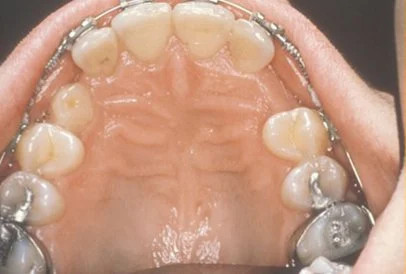

Exposure and bracketing of an impacted cuspid

Impacted canine surgery

The surgery to expose impacted canines takes just about 45 minutes. It is a comfortable procedure that is done under local anesthesia. Mild swelling and soreness may occur for several days following, and can be managed adequately with over the counter pain medicines. During the surgery, the crown of the tooth is uncovered. Depending on the severity of impaction, we may attach a bracket and gold chain to the tooth to “pull” it into place, or we may simply apply a dressing and let it find its own way. It is important to maintain good dental hygiene as part of your home care practice. We will schedule a follow up appointment about a week after surgery to check on your healing.